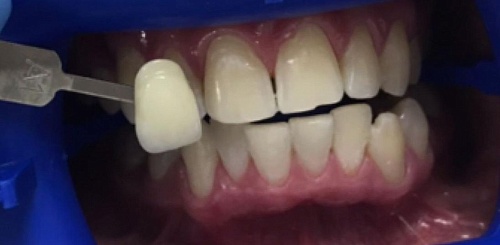

Сохранить зубы и пародонт помогает правильная гигиена полости рта дома и в кресле стоматолога, а также своевременное протезирование и имплантация, которые замещают удаленные зубы и равномерно распределяют жевательную нагрузку, не позволяя костной ткани атрофироваться.